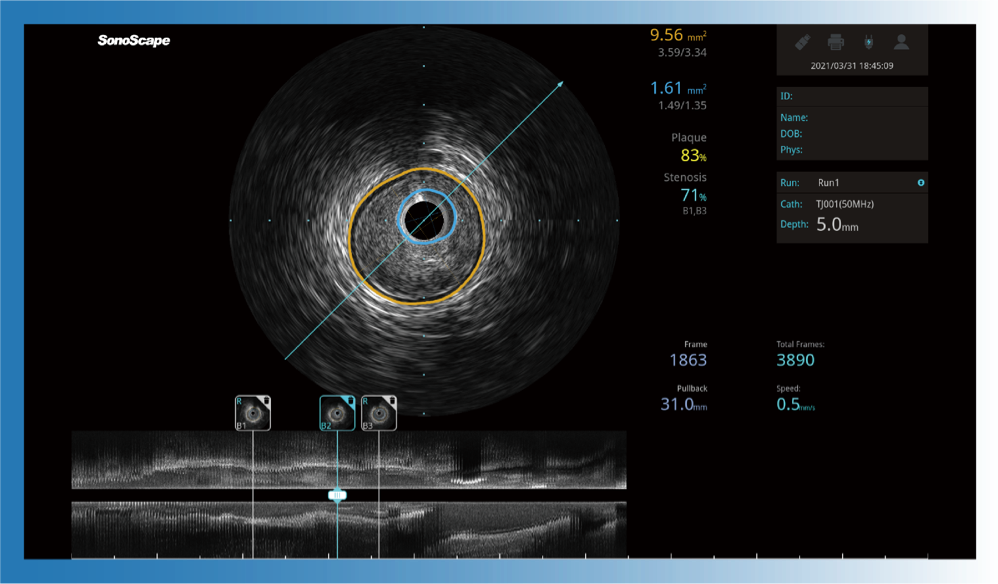

对比传统IVUS导管成像,美狮贵宾会官网宽频IVUS图像的近场支架梁显影更细腻,远场中膜外血管仍清晰可辨,兼顾远中近,兼顾分辨力与穿透深度

一键智能描迹,自动测量斑块负荷、面积狭窄率等指标,准确率高于90%